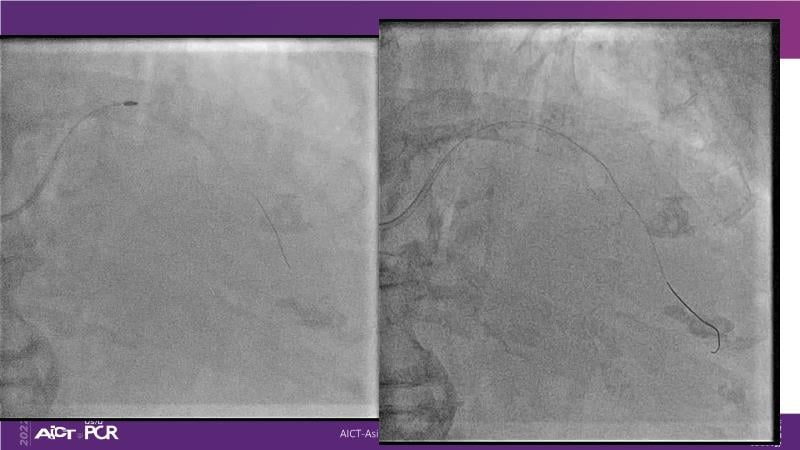

With this session, keep up to date on the evidence, trials and outcome data for intravascular lithotripsy in severely calcified lesions. Learn how to use this technique in real-world patients and understand its role in the treatment algorithm for severely calcified coronary lesions.

- To learn how to use intravascular lithotripsy in real-world patients with severely calcified coronary lesions